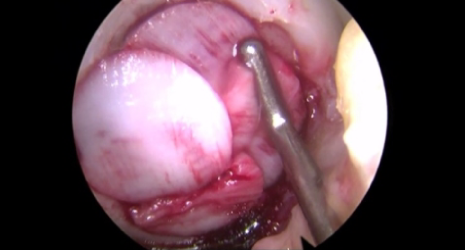

관절내시경으로 손상 부위에 미세천공술을 시행한 뒤, 콜라겐인 콘드로가이드로 덮어주는 재생 치료로 50대 미만에서 시행됩니다. 부착된 콜라겐은 1년 동안 연골재생에 도움이 되는 역할을 한 후, 자연적으로 스며들어 연골로 변화됩니다.

□ 미세천공술로 인한 출혈 속에 발생된 줄기세포를 보호하고 손상된 연골에 부착되게 만들며 자극, 분화시켜 연골재생에 도움

□ 미세천공술만으로 치료가 힘든 큰 연골 결손에 치료 가능

□ 활막에 혈액 유출을 방지하여 높은 안정성

□ 연골형성에 긍정적인 영향을 미쳐 통증 감소